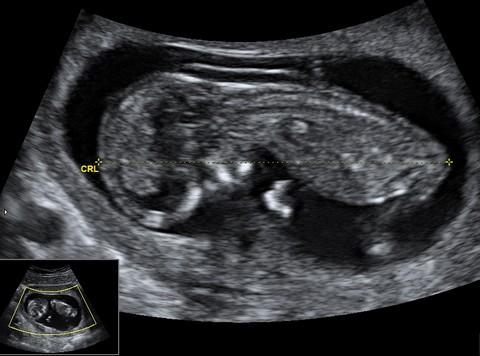

Plod o velikosti 70 mm ve 13. týdnu těhotenství (12+3)

Plod o velikosti 62 mm ve 13. týdnu těhotenství (12+4). Na všech snímcích je snadno rozeznatelná lebka s obličejovou částí, páteř plodu a jeho dolní končetiny.

Plod o velikosti 81 mm ve 13. týdnu těhotenství (12+5)